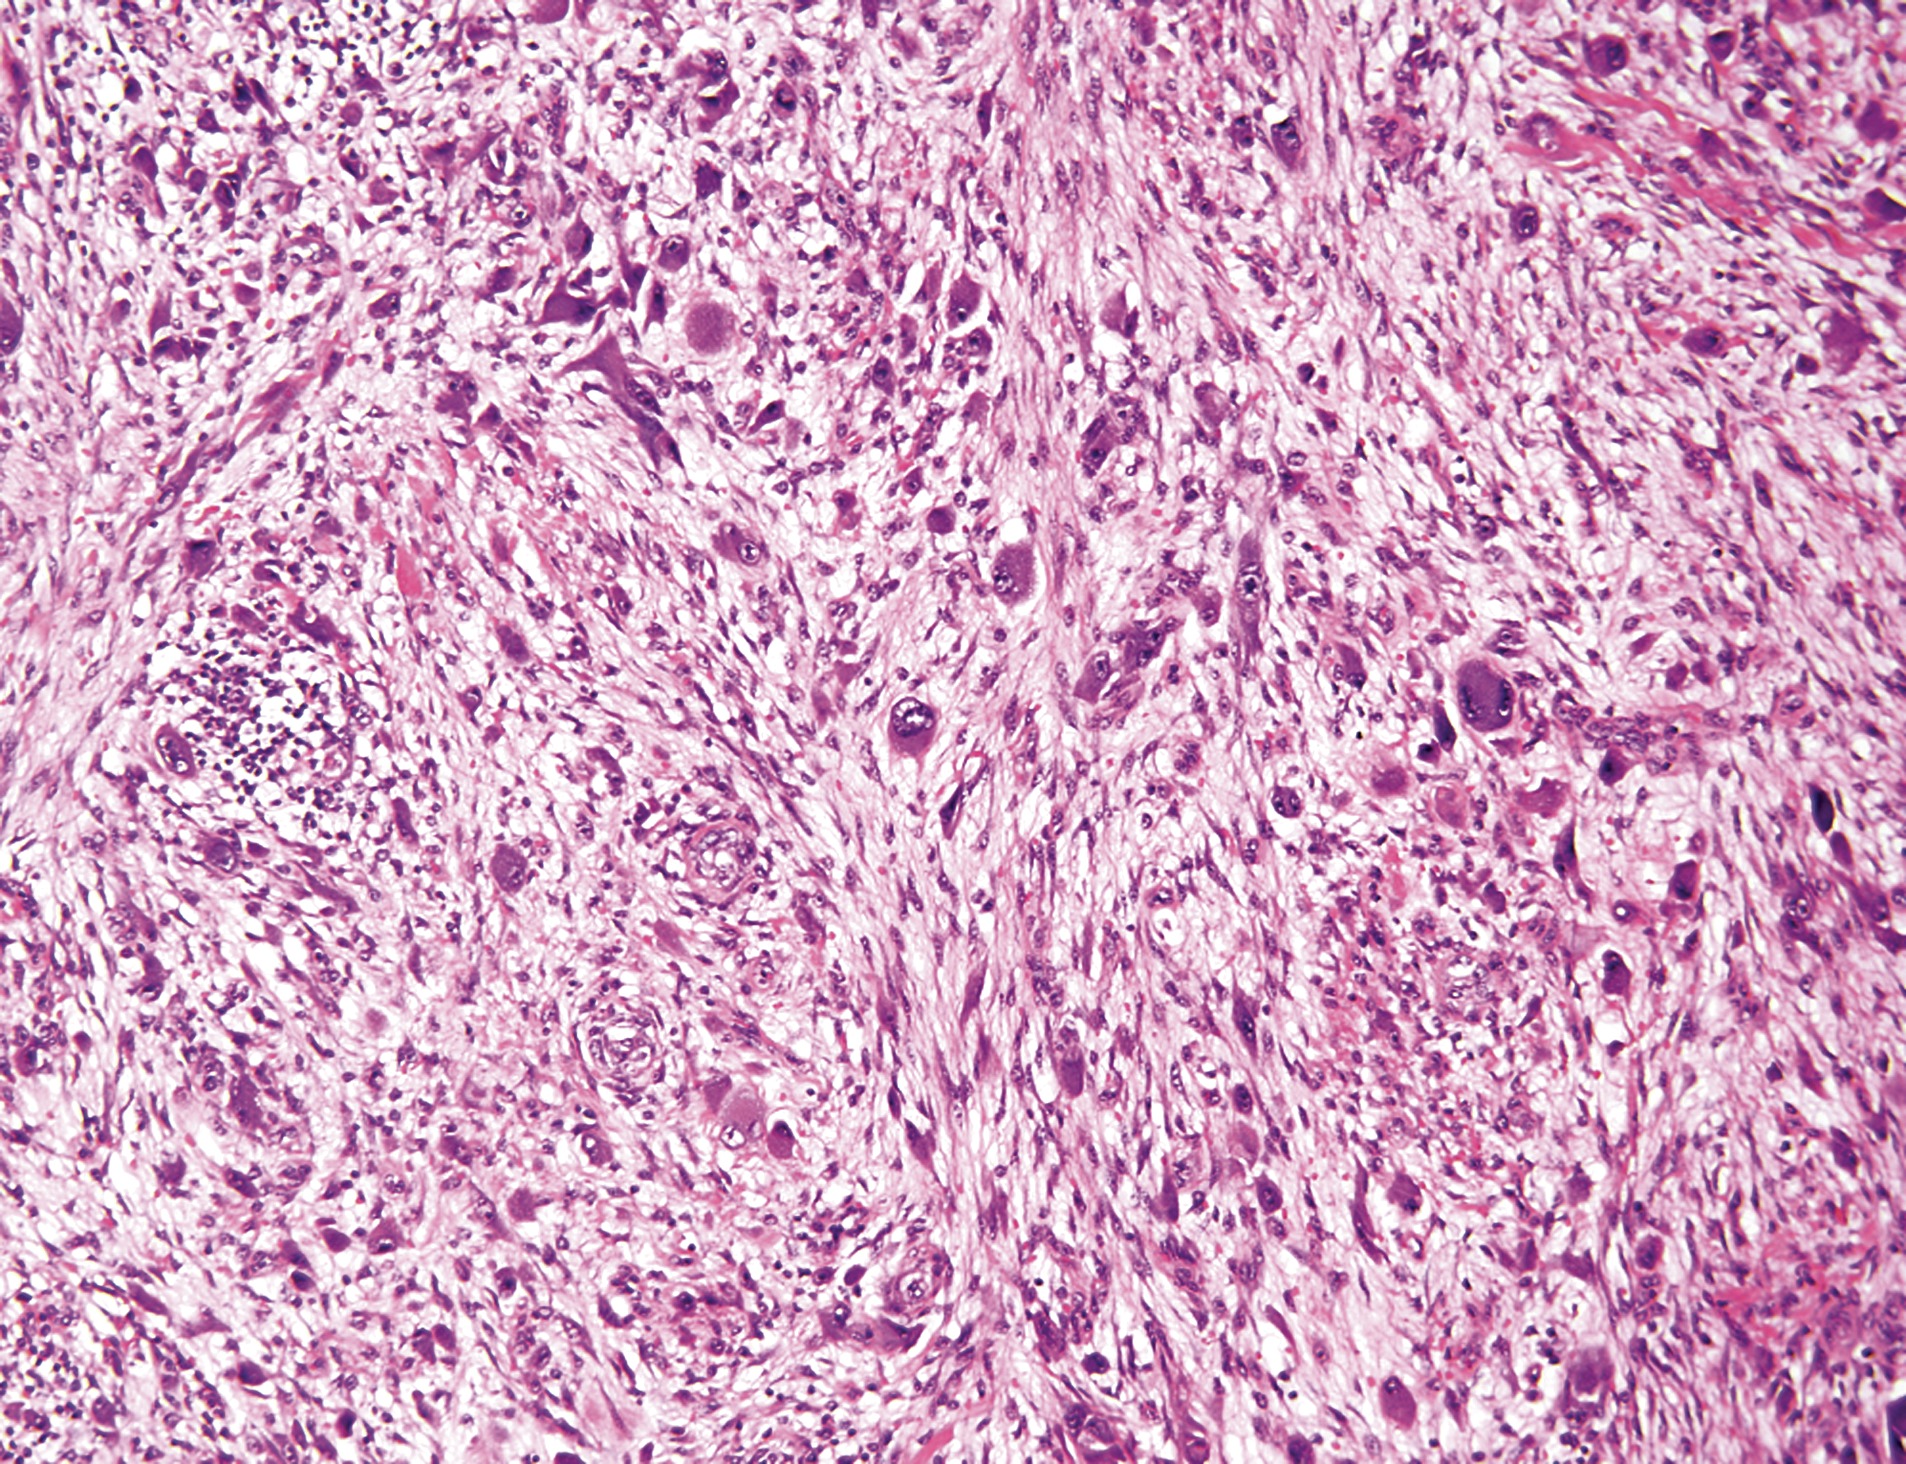

1) Myxofibrosarcome

2) patient âgé, surtout membres inférieurs, un des sarcomes les plus fréquents

3)

Crossance multiondulaire et infiltrative

Cellules pléomorphes ressemblants à des lipoblastes mais remplis de matériel myxoide (pseudolipoblaste)

Vaisseaux curvilinéaires fins

Stroma myxoïde

Mitoses atypiques

4) CD34 et AML focal. S100 négatif

5) Caryotype complexe

6)

Bas grade (ou grade 1) : hypocellulaire

grade intermédiaire (grade 2) : entre deux

haut grade (grade 3) : ressemble à sarcome pléomorphe indifférencié

7)

Myxome : pas de cellules pléomorphes

Liposarcome myxoïde : pas de cellules pléomorphes, pas de lipoblastes

sarcome fibromyxoïde de bas grade : plus fibreux, pas de cellules pléomorphes